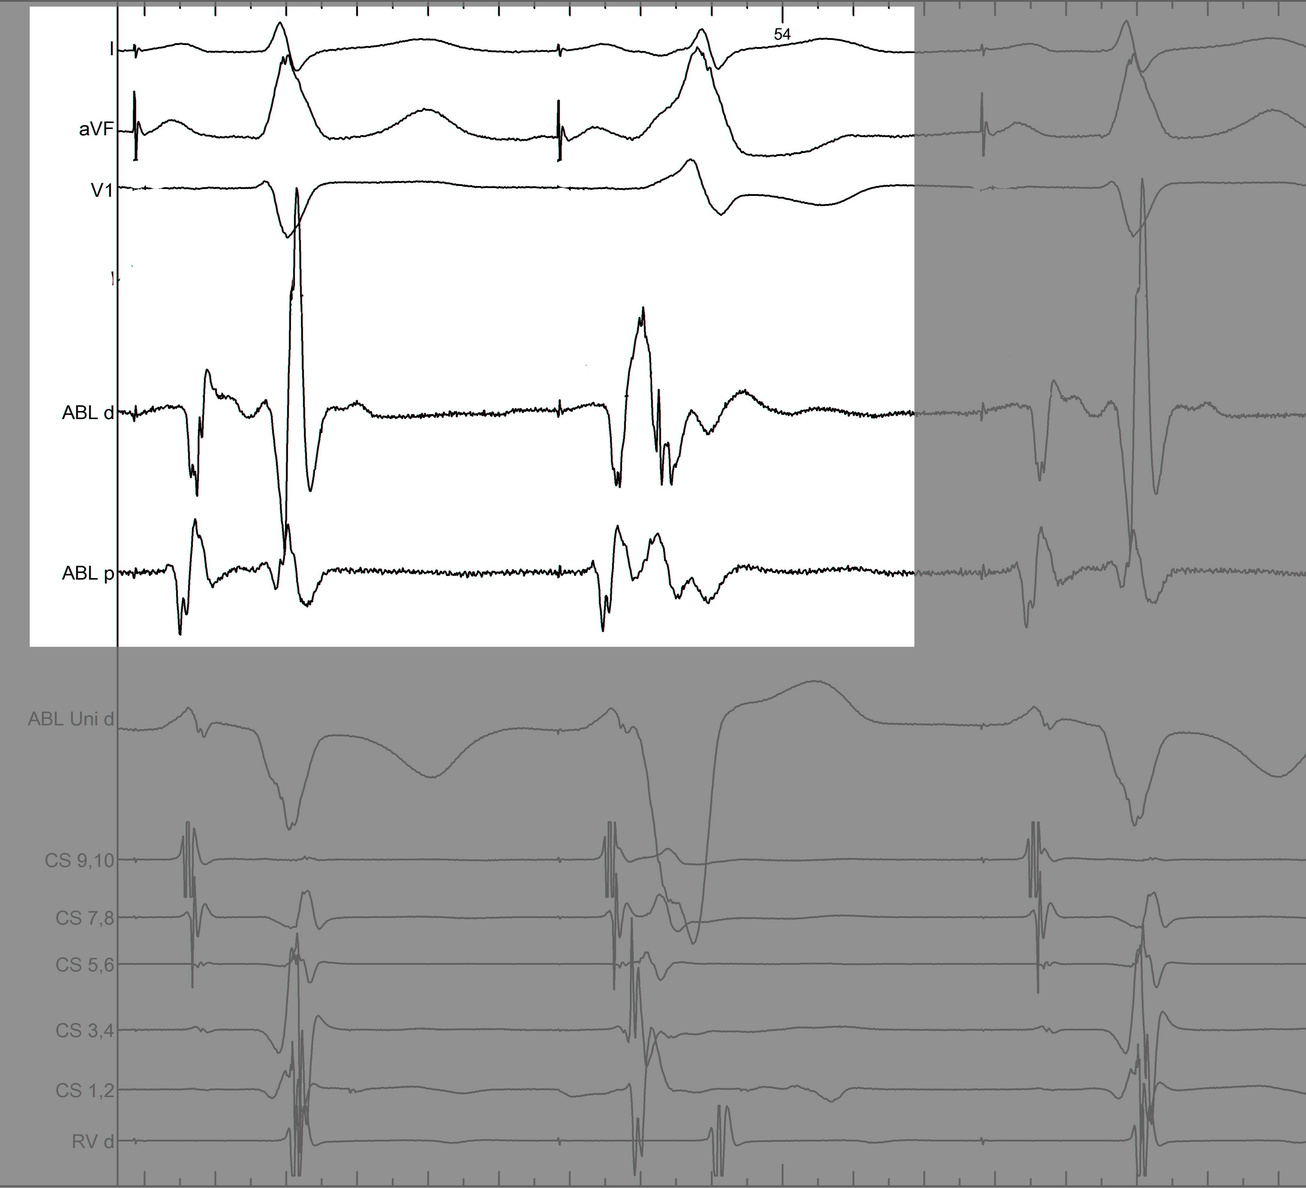

Identify components of the signal

mask4.jpg